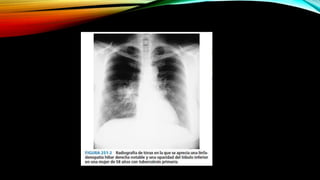

• A esta zona se le llama FOCO DE GHON (foco pulmonar inicial)

INFECCIÓN POR M.TUBERCULOSIS. • Los macrófagos fagocitan a las micobacterias  forma granulomas que mantienen contenido al bacilo. El tejido del interior del medio muere como resultado, proceso conocido como “ necrosis caseosa” • A esta zona se le llama FOCO DE GHON (foco pulmonar inicial) • Aunque M. tuberculosis puede sobrevivir en su interior, su crecimiento es inhibido por : - Por las baja presión de oxígeno. - La presencia de un ph ácido Pueden permanecer en estado latente durante meses años o en más del 90% todas las vida.